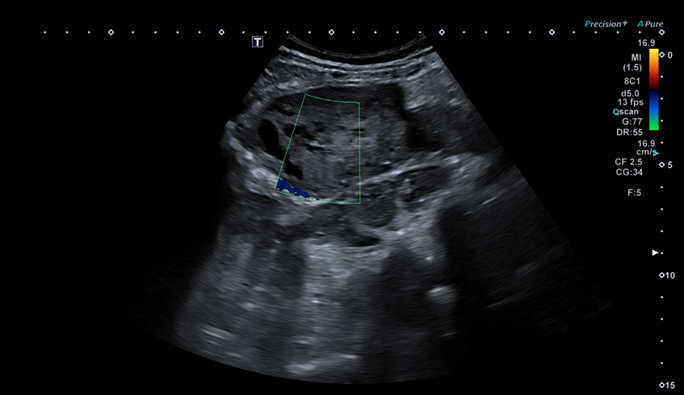

Se completa la exploración en la consulta de Atención Primaria, con ecografía a pie de cama donde se visualiza una imagen de ecoestructura heterogénea, con zonas hiperecoicas y zonas anecoicas, yuxtarrenal izquierda y que capta Doppler en algunas zonas.